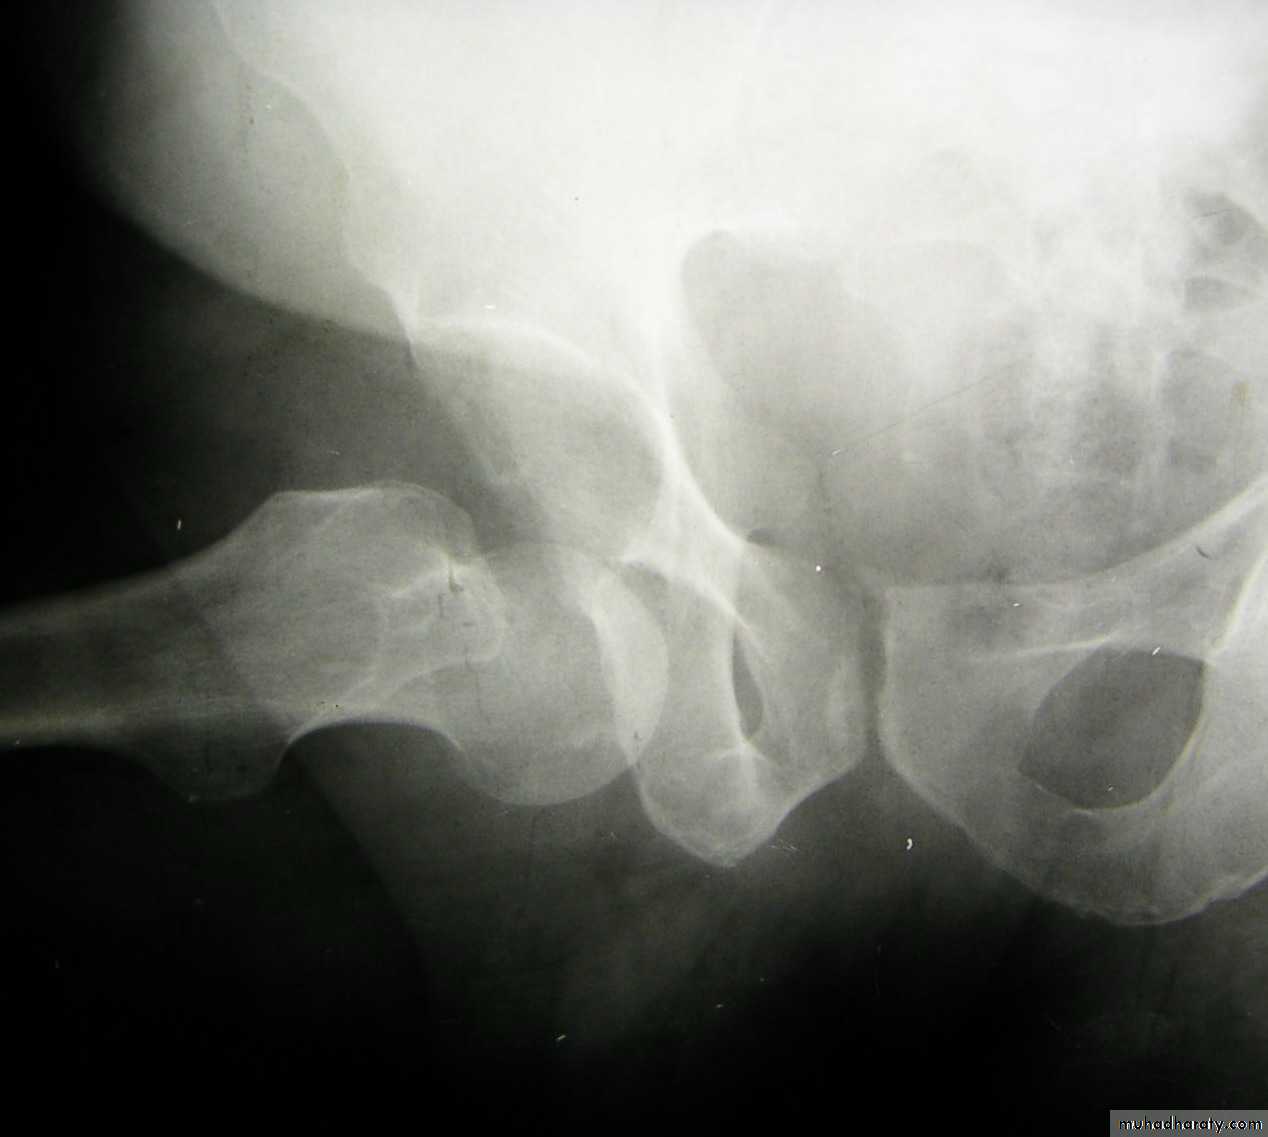

Radiological examination

two questions must be answered.

Is there a fracture?

Is it displaced ?

:Radiological classification

GRADE 1

:the femoral head is in its normal position or tilted into valgus and impacted on the femoral stump.

GRADE 2

The femoral head is normally placed and the fracture line may be difficult to diagnosed

GRADE 3

The femoral head tilted out of position and the trabecular marking are not in line with those of innominate bone.

GRADE 4

The femoral head trabeculae are normally aligned with those of innominate bone.